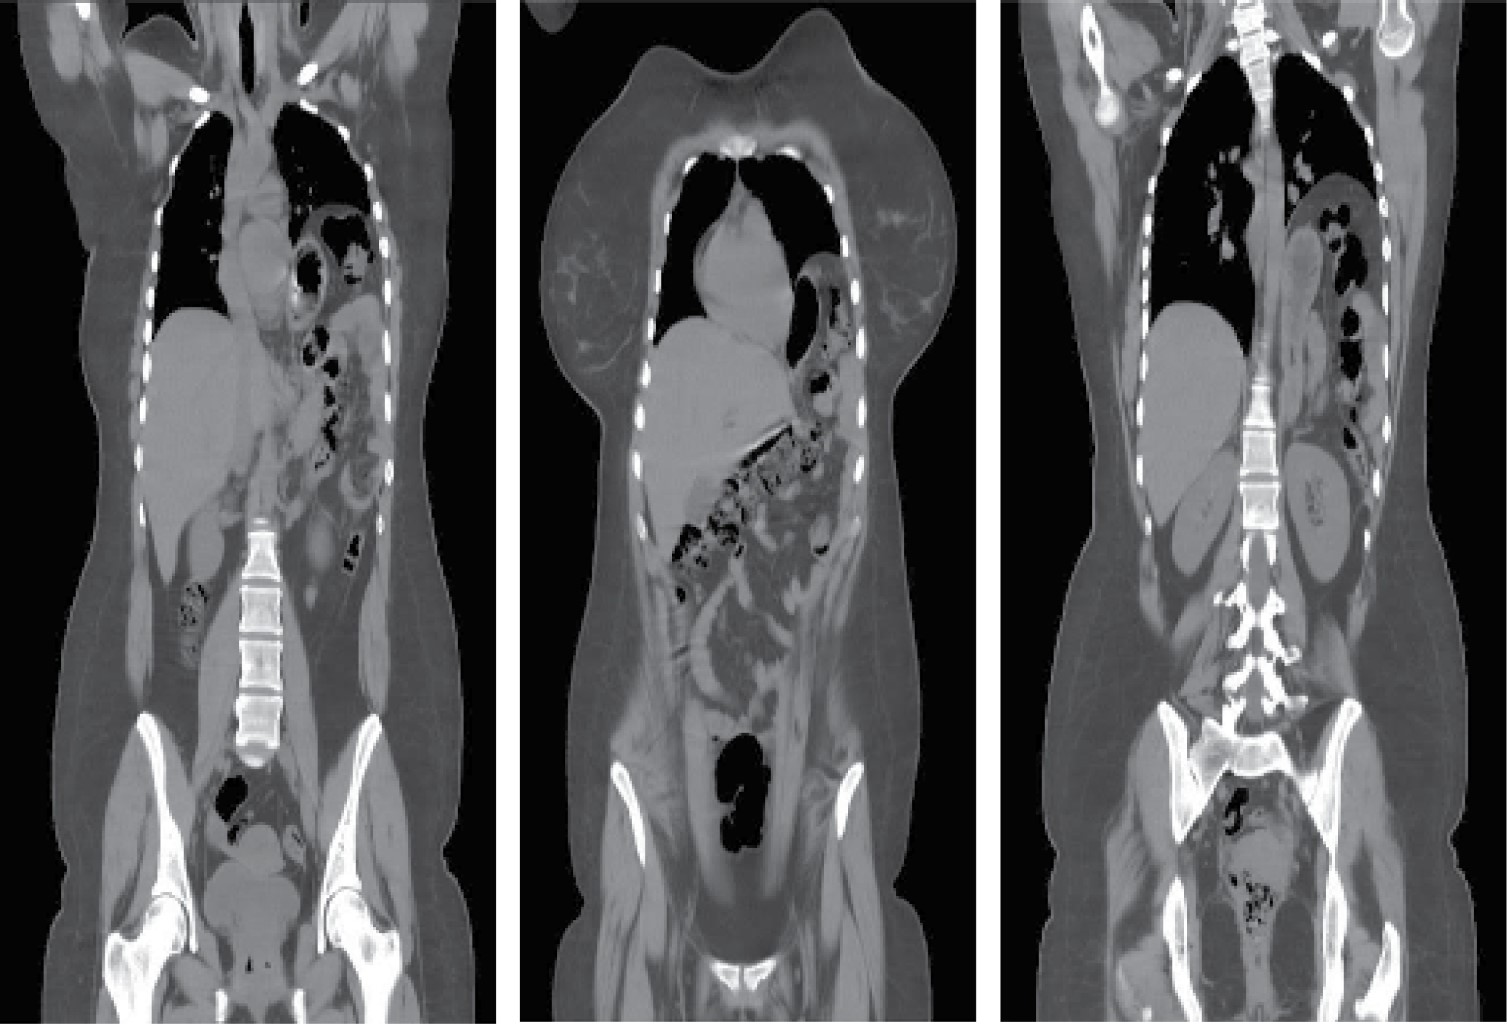

Radiografía de tórax a su ingreso con imagen radiopaca basal izquierda con niveles hidroaéreos (Figura 1), por lo que se solicita estudio tomográfico que confirma la presencia de una hernia diafragmática izquierda con colon, bazo, estómago e intestino delgado dentro de su contenido (Figura 2).

Figura 2